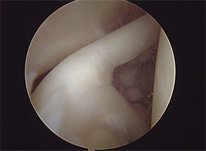

Mostramos ao lado um caso de um paciente masculino de 33 anos com uma lesão osteocondral cística do côndilo femoral medial do joelho. O paciente apresentava dores de forte intensidade e derrames articulares de repetição.